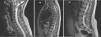

ResultsA total of 167 cases of ISCGG were found, including our own. In our sample, 52% of patients were female and the most commonly affected age group was 0-9 years of age (35% of patients). Motor deficit has been found to be the main symptom in a larger proportion of adults patients versus pediatric patients. On X-ray, this tumor shows greater hyperintensity and contrast uptake than astrocytomas and ependymomas, as well as a higher percentage of intratumoral cysts. The BRAFV600E mutation is less common in spinal as opposed to supratentorial gangliogliomas. Surgery with complete resection is the treatment of choice. Only 19% of the patients in the sample received radiotherapy, and only 9% received chemotherapy as their only line of treatment.

ResultadosSe encontraron un total de 167 casos de GGEI, incluyendo nuestro caso. En nuestra muestra, el 52% de los pacientes pertenece al sexo femenino, siendo la década de edad más afectada la que va de los 0 a los 9 años (35% de los pacientes). El déficit motor se establece como síntoma principal en pacientes adultos en mayor proporción que en pacientes pediátricos. Radiológicamente, este tumor se presenta con mayor hiperintensidad y captación de contraste que los astrocitomas y los ependimomas, así como un mayor porcentaje de quistes intratumorales. La mutación BRAFV600E es menos frecuente en los gangliogliomas espinales que en los supratentoriales. La cirugía con resección total es el tratamiento de elección. Solamente el 19% de los pacientes de la muestra recibieron radioterapia y solo el 9% quimioterapia como única vía de tratamiento.